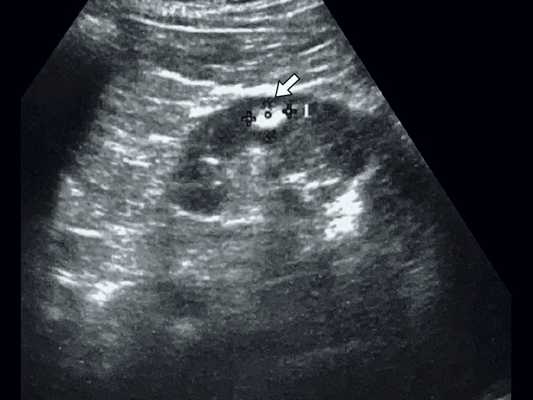

При классической картине АМЛ в почке определяется гиперэхогенное (по отношению к паренхиме почки) образование с четкими контурами, не дающее акустической тени, округлой формы, акустическая плотность которого соответствует плотности жировой ткани, структура опухоли однородная во всех отделах (рис. 2, 3).

В паренхиме почки визуализируется гиперэхогенное образование с четкими контурами, небольшого размера, без акустической тени.